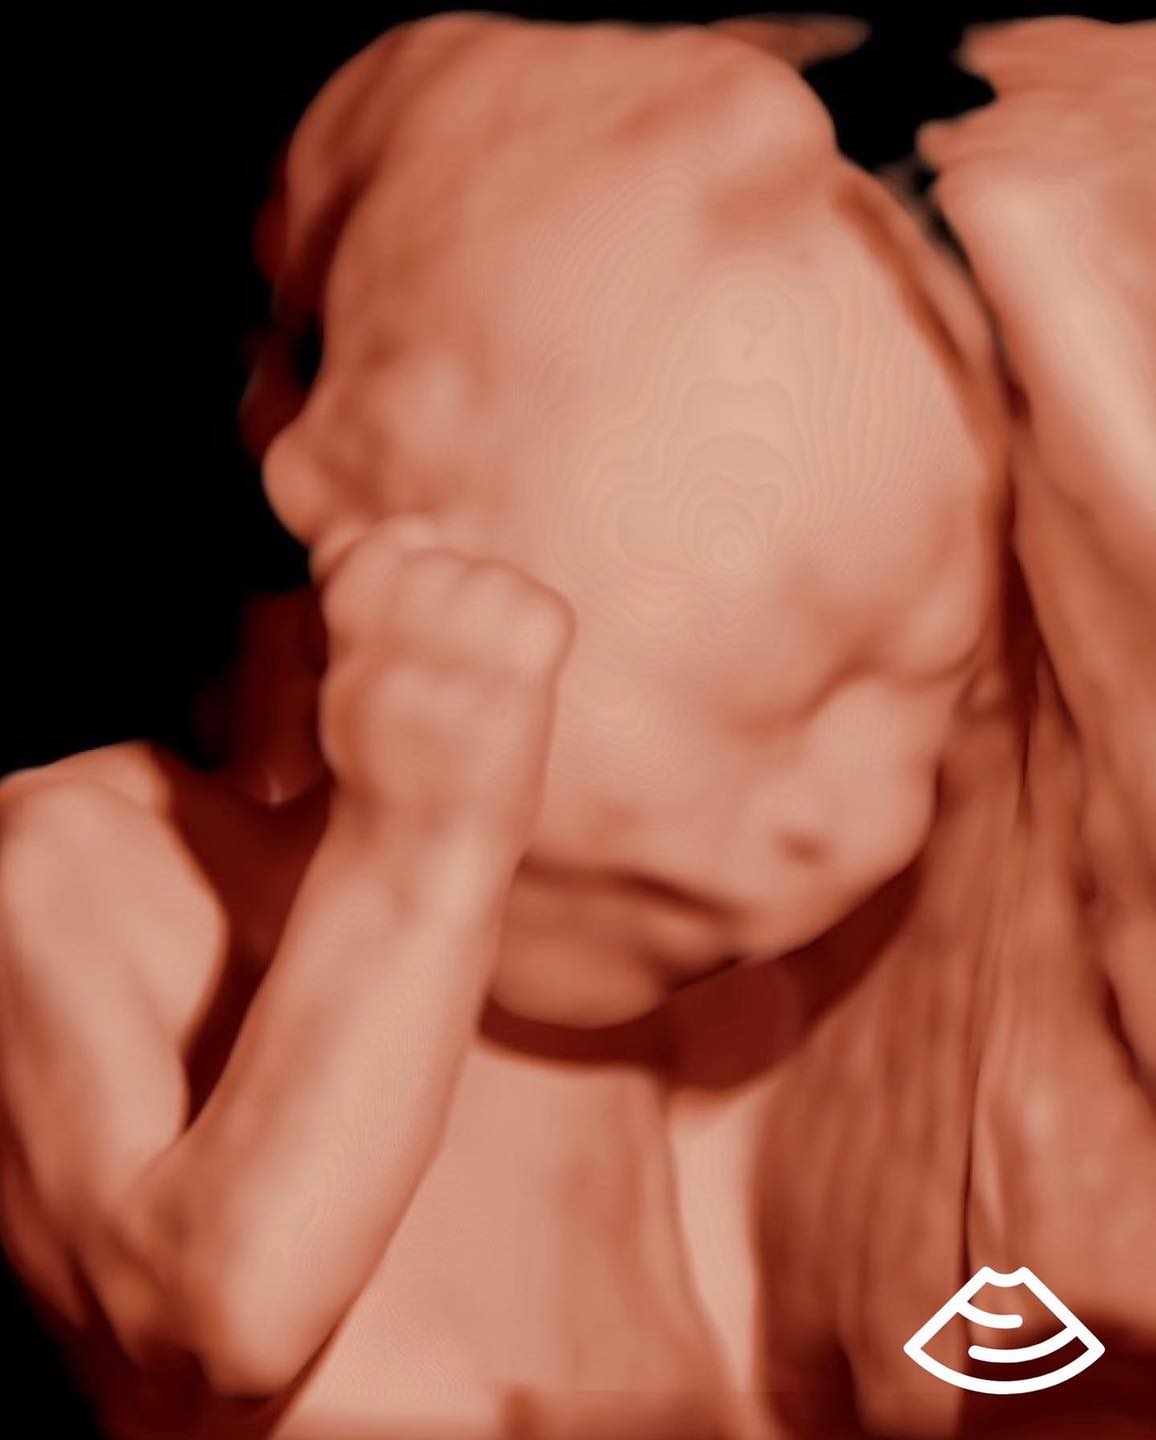

Máy siêu âm tính tuổi thai có chính xác không? Siêu âm là phương pháp tính tuổi thai chính xác nhất dựa trên cơ sở khoa học về thai kỳ. Thời điểm để siêu âm lý tưởng nhất, cho kết quả ngày dự sinh chính xác nhất là khi thai đợc 8 – 13 tuần 6 ngày (theo Hiệp hội siêu âm sản phụ khoa thế giới).

Đo siêu âm thai nhi trong tam cá nguyệt thứ nhất cho ước tính chính xác nhất về tuổi thai khi thiếu các thông tin khác. Khi ngày thụ thai không xác định và …

Em bé có thể được siêu âm sớm nhất là 5 hoặc 6 tuần sau kỳ kinh nguyệt cuối cùng của người mẹ . Đo tuổi em bé bằng siêu âm là chính xác nhất …